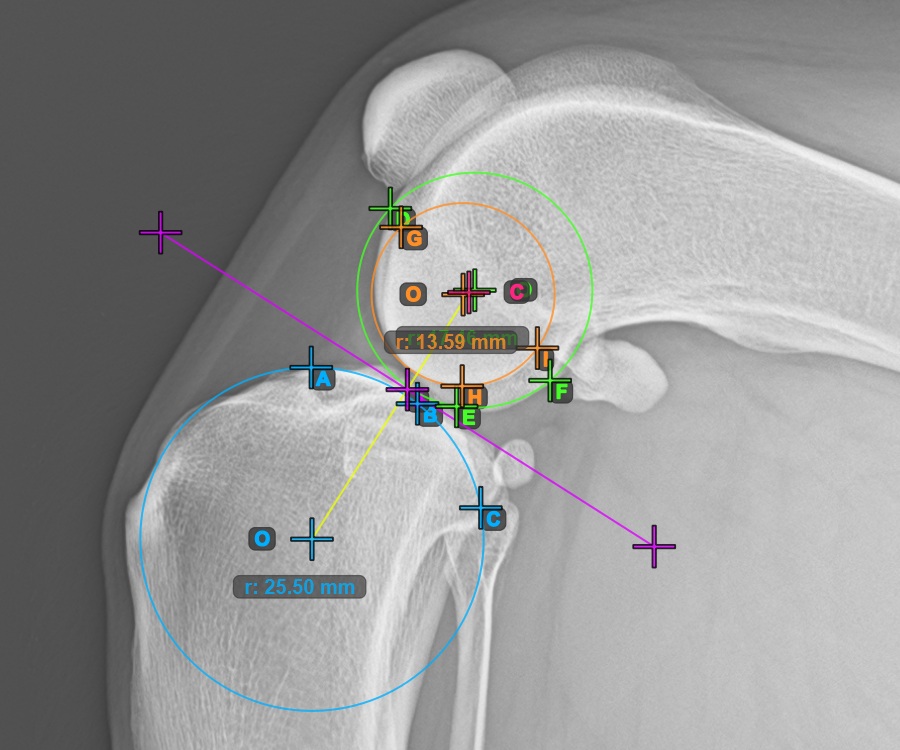

Start the measurement by marking the three points on the Condylus Medialis Tibialis.

Mark the three points on the main condylus of the tibial bone (Medialis Tibialis). Regardless of the order, make sure to mark the most cranial point, the most caudal point and the midpoint of the Medialis Tibialis. A circle will be automatically constructed based on the three placed points.

The image below represents a typical placement of the three points on the Condylus Medialis Tibialis.